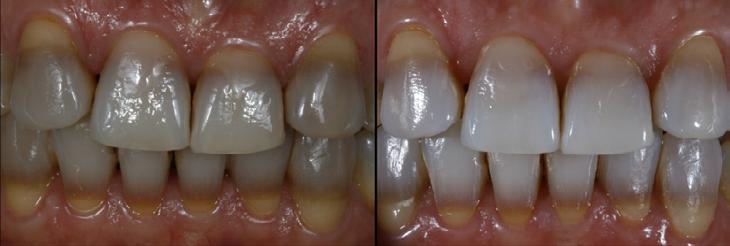

Restoring incisal wear and closing diastema with G-aenial A’CHORD. Courtesy of: Dr Aleksandra Slacan, Poland

Reshaping of teeth and diastema closure with G-aenial A’CHORD. Courtesy of: Dr Andres Silva, Spain